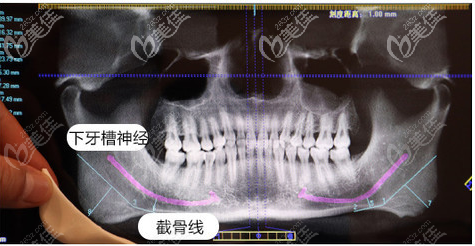

做磨骨手術(shù)前醫(yī)院會進行數(shù)字化設(shè)計,怎么截,截骨截多少,醫(yī)生都會在設(shè)計后為我詳細講解。

這是護士小姐姐給我拍的高俊明磨骨手術(shù)過程圖。